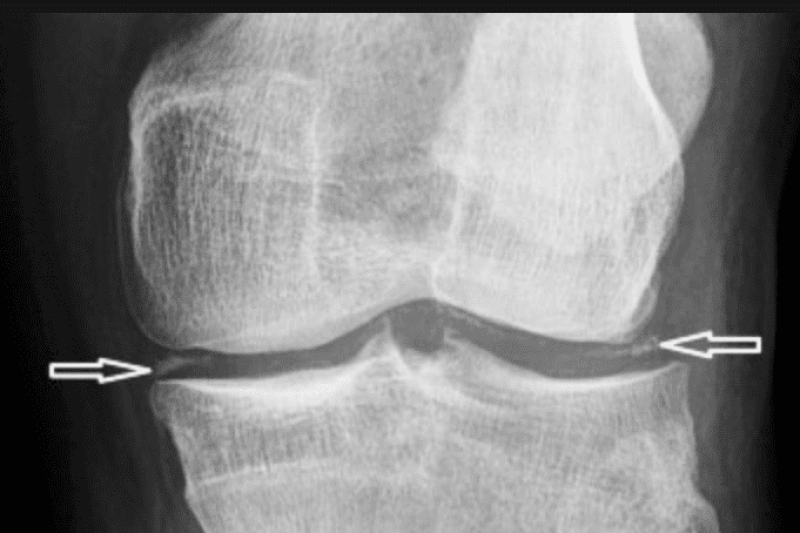

What is Pseudogout “false gout”? Calcium Pyrophosphate Deposition (CPPD) also known as Pseudogout, is a joint problem caused by crystals of calcium salt called Pyrophosphate that are deposited …